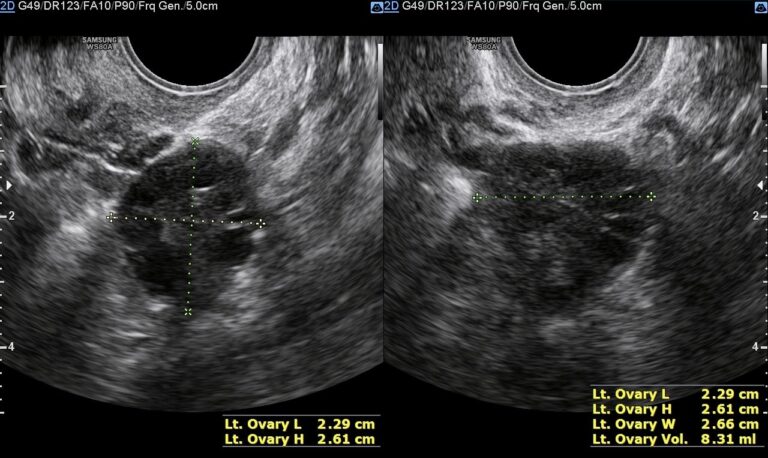

Folículo no ovário: desvendando este mistério

A presença de folículo no ovário pode ser algo intrigante, vamos aqui ajudar você a desvendar o mistério…